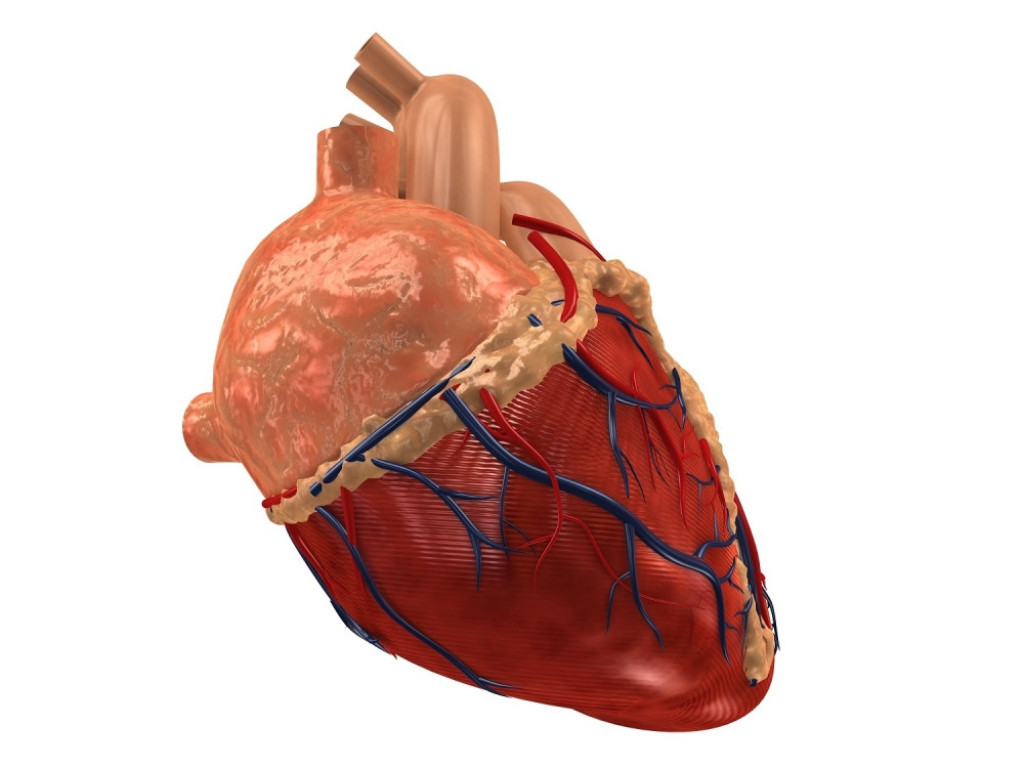

Shutterstock